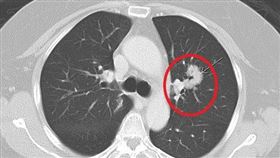

她肺腺癌第四期 靠這治療重回健身房

一名年約50歲的女性病患熱愛有氧運動,日前發現自己久...